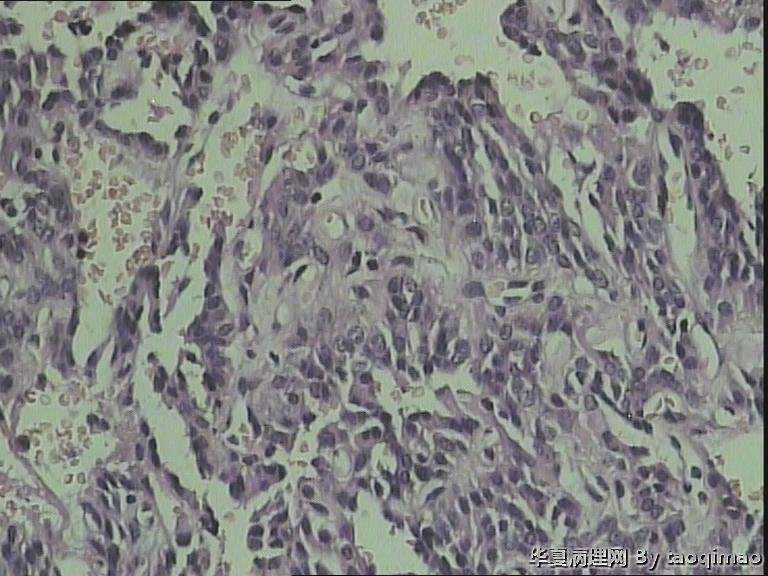

椎管内肿物

女 49岁,腰部及右下肢麻木坠胀1月

术中在椎管内,拨开马尾神经,可见椎体后缘约2*1cm实性肿物,与马尾神经粘连,边界清晰。

肉眼:红褐色不规则组织一块,2.5*1cm。剖面暗红兼灰白质软。

考虑粘液乳头型室管膜瘤。好发部位为圆锥和终丝

1、瘤细胞低柱状或立方形,大小形态较一致,围绕血管形成乳头状或假菊形团样,部分胞浆突起形成明显的无核区。

2、脊髓是室管膜的好发部位,经常会有相应的运动和感觉神经障碍。

3、鉴别:脉络丛乳头状瘤。免疫组化:室管膜瘤 CK(-),EMA(+),GFAP(+);而脉络丛乳头状瘤CK(+),GFAP(-).

片中可以看见假菊形团结构,结合部位,应该是室管膜瘤。学习了。

各位老师不好意思,忘记把u盘拿回来了,今天做了5项免疫组化,CgA(+),S-100(+),CD34(-),EMA(-),Ki-67(-)。请各位老师进一步指教,我们没有CK,所以做的EMA。

粘液乳头型室管膜瘤。此病人发病部位特殊(马尾),组织学(乳头+粘液)也非常典型,是个很好的病例,可以作为教学片了,明确诊断应该没问题。

本病本质上为生长缓慢的胶质瘤(WHO I级)。免疫组化:GFAP(+),S-100(+),Vim(+),CK(-)。

粘液乳头型室管膜瘤几乎毫无例外地发生于马尾终丝。

室管膜瘤EMA应为阳性,本例为阴性?GFAP?

本例乳头状结构明显,但黏液背景不明显。

不典型病例。